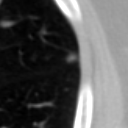

The current study focuses on lung nodule retrieval from a database of CT scans, where patches taken from CT slices of pulmonary nodules are to be mapped into an embedding. LIDC-IDRI [5] is a dataset of thoracic CT scans of 1,010 patients. All the scans were annotated by up to four radiologists, where each one identified, segmented and evaluated separately the lung nodules of a diameter above . Their evaluation also included ratings for a set of 9 characteristics: Subtlety, Internal structure, Calcification, Sphericity, Margin, Lobulation, Spiculation, Texture and Malignancy. The rating system was based on a discrete score of 1-5. Four examples of nodule patches are illustrated in Figure 2: 2 benign (a, b) and 2 malignant (c, d). A rounded vector of the mean rating is bellow each nodule, with the characteristics ordered according to the listing above. The most prominent difference between a and b is the calcification: 3 (solid) and 6 (absent) accordingly. d compared to c has a more defined margin, is more lobulated, but less spiculated. The malignancy score is used to define malignancy classes: score of 1-2 is benign, score of 3 is unknown, and a score of 4-5 is malignant.

(a) Benign

3, 1, 3, 3, 4, 3, 1, 5, 1

(b) Benign

3, 1, 6, 5, 5, 1, 1, 5, 2

(c) Malignant

5, 1, 6, 3, 3, 4, 1, 5, 5

(d) Malignant

4, 1, 6, 3, 4, 2, 2, 5, 4